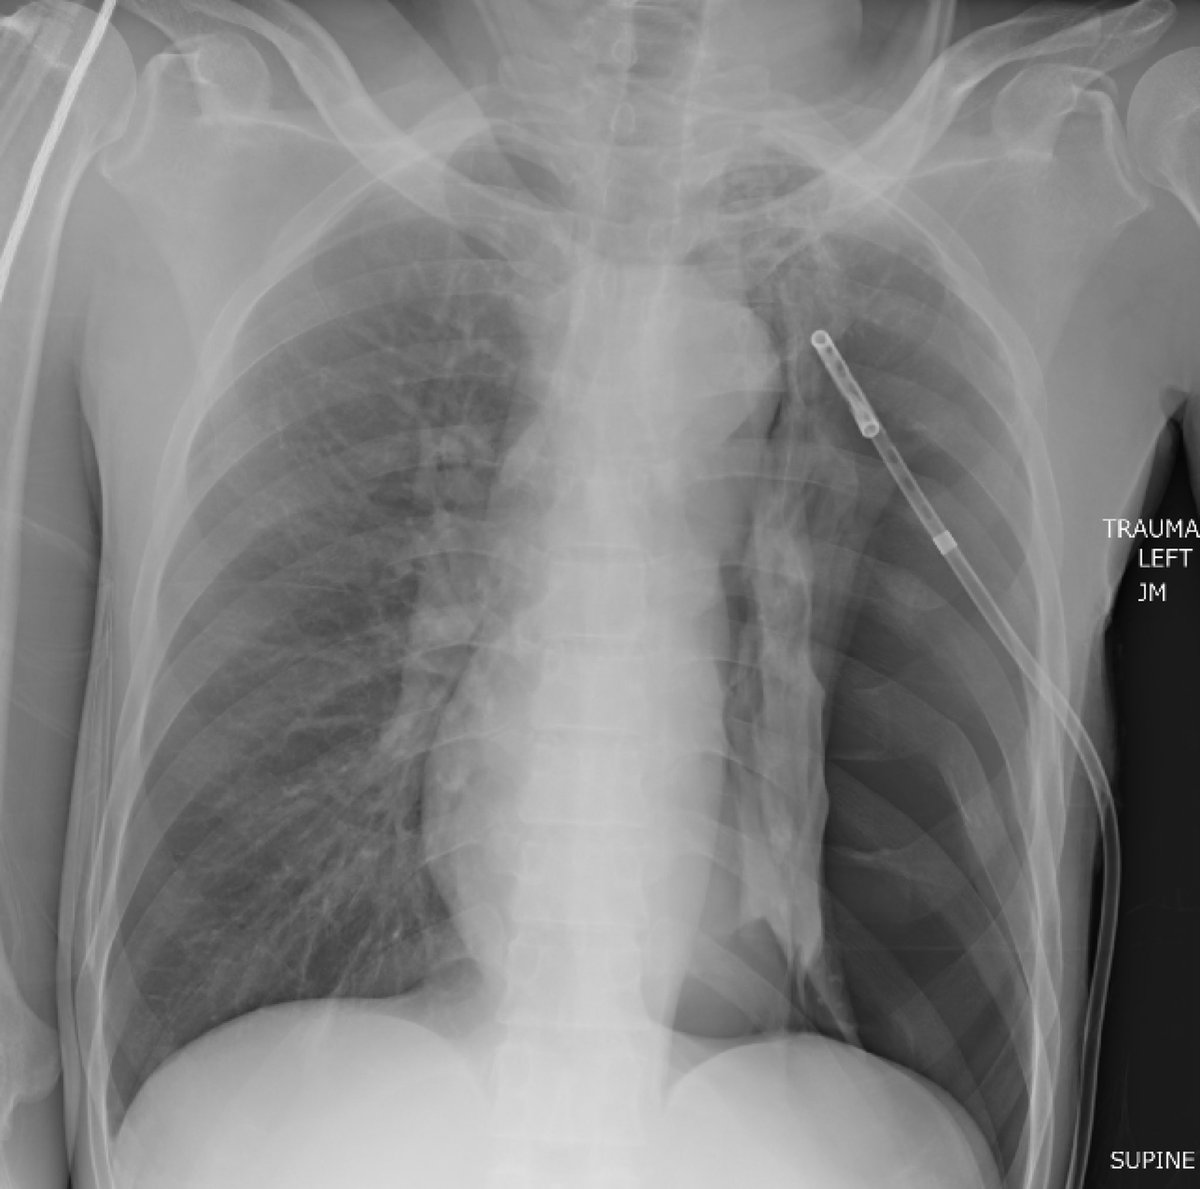

Here’s an impressive Chest X-Ray from the Trauma Bay What’s the diagnosis?